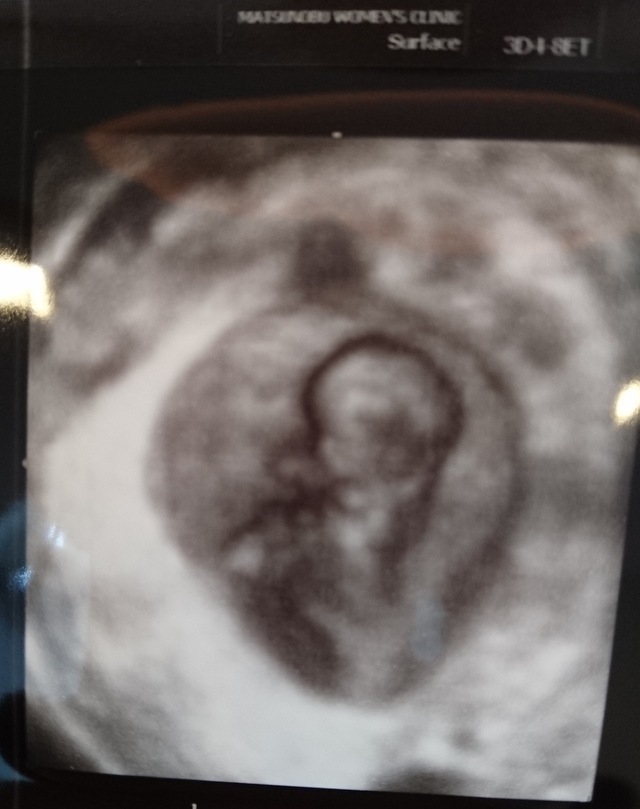

9週1日(9w1d・女の子)|きういゆず さん(26歳)

エコー写真撮影時のエピソード:

初めて旦那さんと検診に行った日のエコーです。

ハートの中に亀さんがいるようなエコーで旦那さんと笑いあったことを思い出します。 まだまだ人間らしい形をしていないのに、こんなに愛おしく感じれるのかと感動しました。